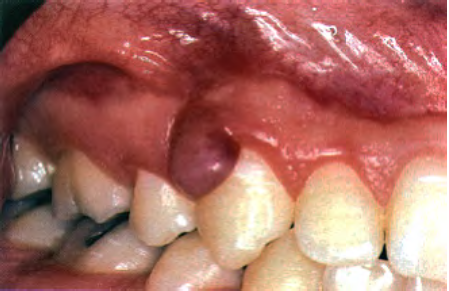

What is this clinical finding?

A parulis

It is not a pyogenic granuloma

A parulis is a proliferation of granulation tissue at the opening of a sinus tract

When the infection breaks through the alveolar bone and presents itself,

it will sometimes cause this proliferation of granulation tissue